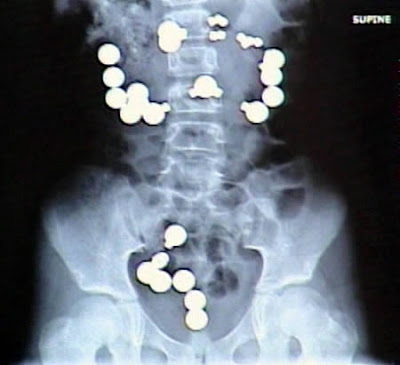

The Most Bizarre X-Rays

8-year-old Haley Lents of Indiana swallowed 10 magnets and 20 steel balls from a Magnetix toy set. The magnets and balls attracted one another within her digestive tract, ripping a total of eight holes in her intestines and forcing her parents to rush her to the hospital for emergency surgery. Lents later told reporters that the magnets and steel balls "looked like candy."